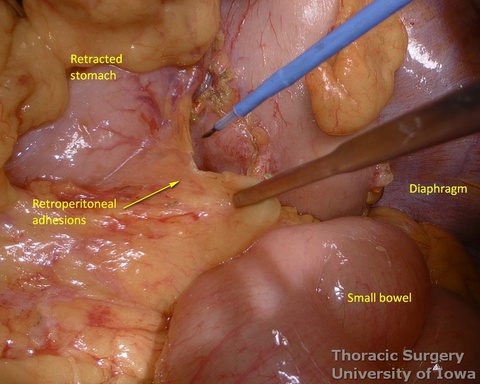

- The mediastinum is entered with the combination of sharp and blunt dissection. Note that postradiation adhesions become denser 4-6 weeks after neoadjuvant treatment.

- Posterior adhesions of the stomach are taken down.

- Peritoneum is incised, protecting the splenic artery and pancreas. 1-2 mm posterior gastric artery, originating from the proximal splenic artery fs present (in half of individuals) and is divided.

- Once the stomach is mobilized and reflected anteriorly, the left gastric vascular pedicle is identified and dissected close to the origin for adequate lymphadenectomy. Care is taken to not injure splenic artery and pancreas.

- Postradiation adhesions may be dense.